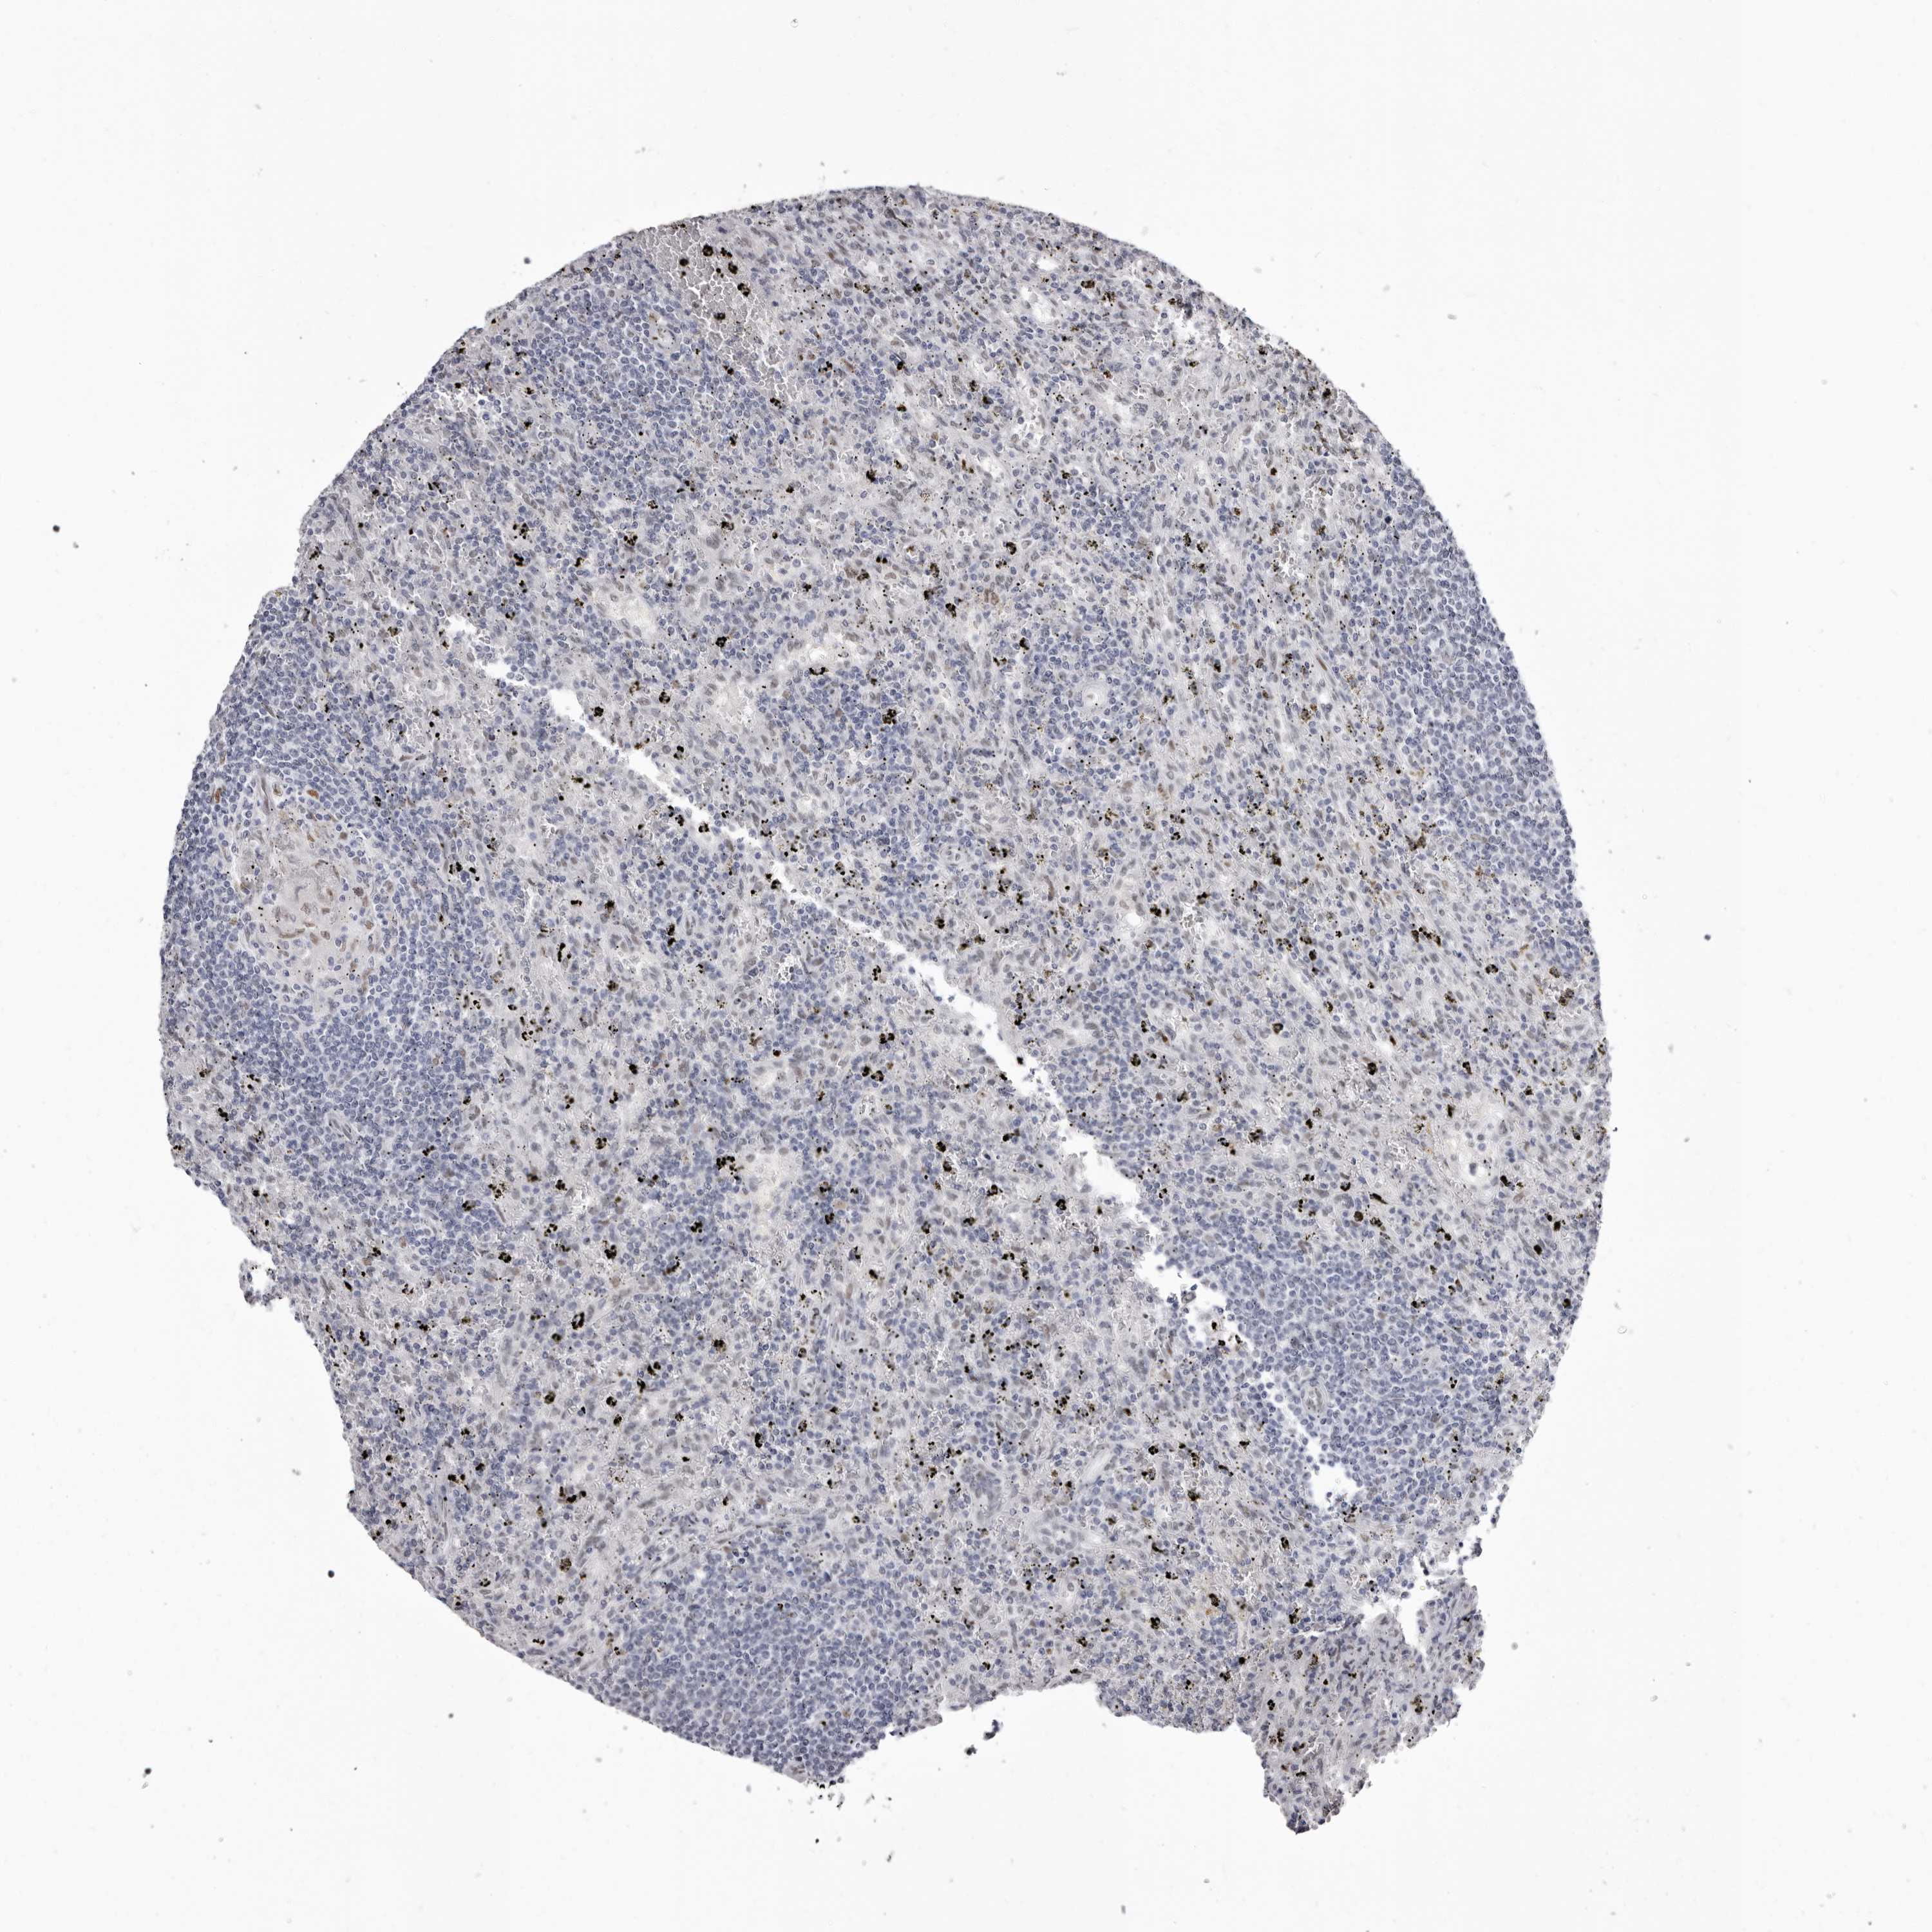

CANCER LYMPHOMA Show tissue menu

LYMPHOMA - Protein expressioni

A mouse-over function shows sample information and annotation data. Click on an image to view it in a full screen mode. Samples can be filtered based on level of antibody staining by selecting one or several of the following categories: high, medium, low and not detected. The assay and annotation is described here.

Each image is clickable and will lead to virtual microscopy that enables deeper exploration of all samples and also displays staining intensity scores, fraction scores and subcellular localization as well as patient and tissue information for each sample.

Antibody HPA028461

Hodgkin's disease, NOS

Malignant lymphoma, non-Hodgkin's type, High grade

Malignant lymphoma, non-Hodgkin's type, Low grade